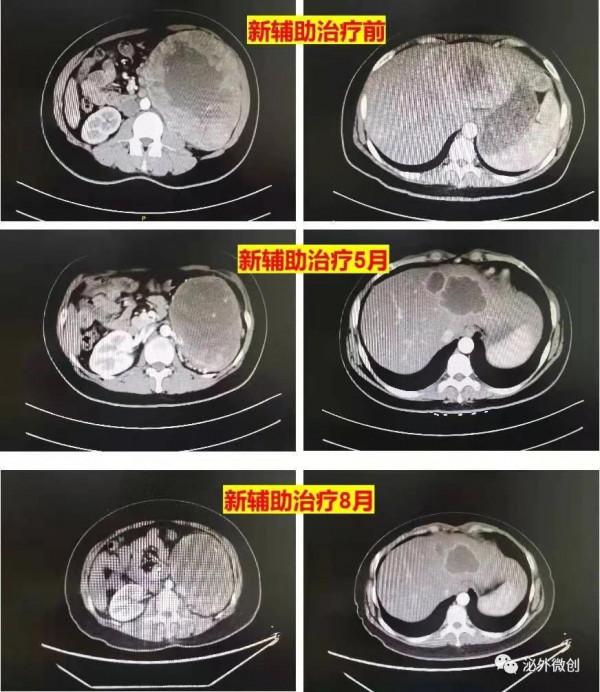

患者女性,32歲,因腹部不適1月於2021年3月入院,入院後完善CT及MRI等檢查提示左腎巨大佔位16*12cm,肝臟多髮結節,最大9.8*7.5cm,考慮左腎腫瘤並肝臟轉移,行左腎腫瘤穿刺活檢提示腎透明細胞癌,給予TKI類藥物培唑帕尼片 0.8 qd 靶向治療,並且行腎動脈栓塞術,治療後五個月複查腎臟腫瘤明顯縮小,肝臟轉移灶也明顯縮小液化,八個月複查腫瘤沒有繼續明顯縮小,故決定手術切除腎臟原發病灶,2021年12月給予行後腹腔鏡下左腎切除術,術後繼續給予靶向治療。

新輔助治療前後CT病灶對比